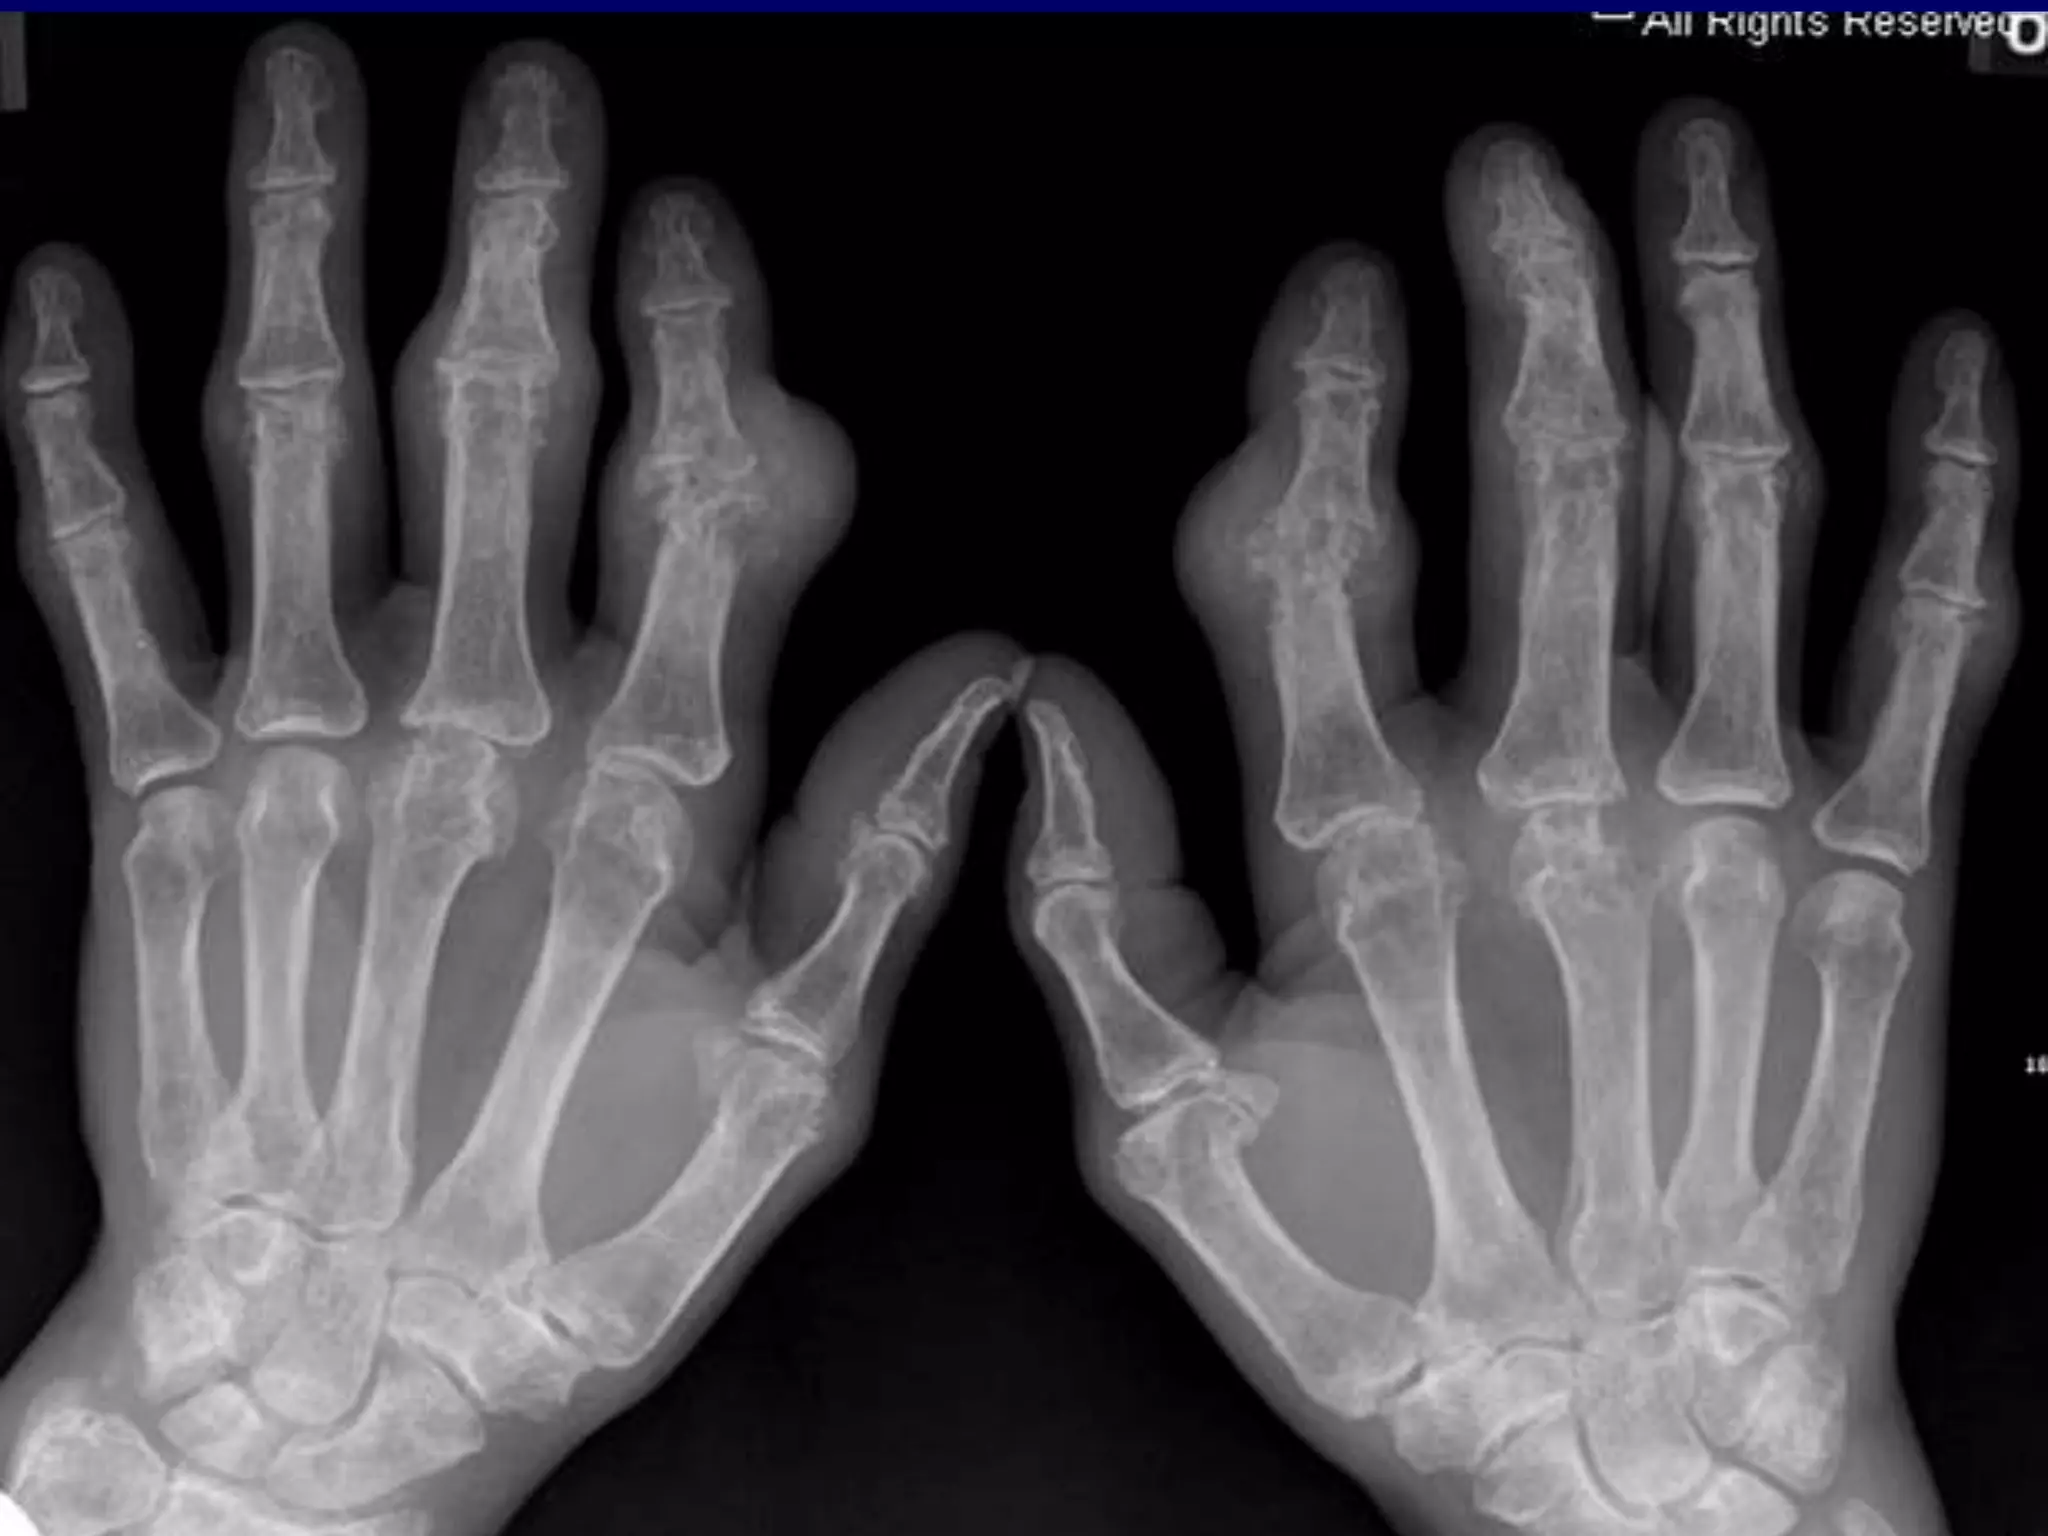

 Advanced RA. Radiograph of the hand

shows severe destruction and

mutilation of the radiocarpal,

intercarpal, carpometacarpal, and

metacarpophalangeal joints.

Intercarpal ankylosis is noted.

 There is also subluxation and deviation

of the fourth and fifth fingers